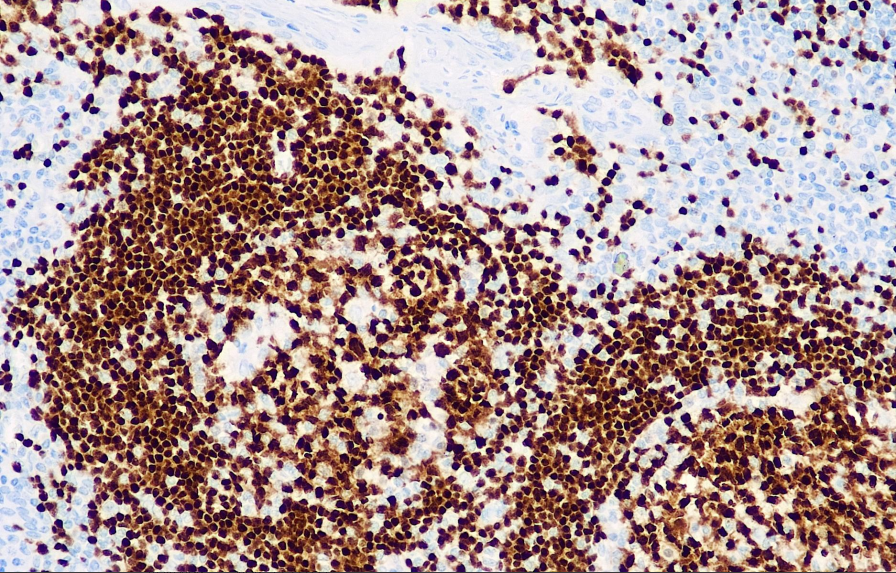

Positive control: tonsils

Pax-5 is a B-cell-specific activating protein that exists in the nuclei of B cells from early B cells to mature B cells and is not expressed in plasma cells. All B-cell-derived tumors (except plasmacytoma) were positively expressed; Negative expression of T cells and their sources in tumors; Weak expression of R-S cells in typical Hodgkin's lymphoma. This antibody is mainly used in the research of B cells and tumors of their origin.

The Pax-5 antibody reagent can specifically bind to the Pax-5 molecular antigen. The immunohistochemical kit containing the Pax-5 antibody reagent is suitable for the precise diagnosis of B-cell lymphoma (such as B-ALL and diffuse large B-cell lymphoma).